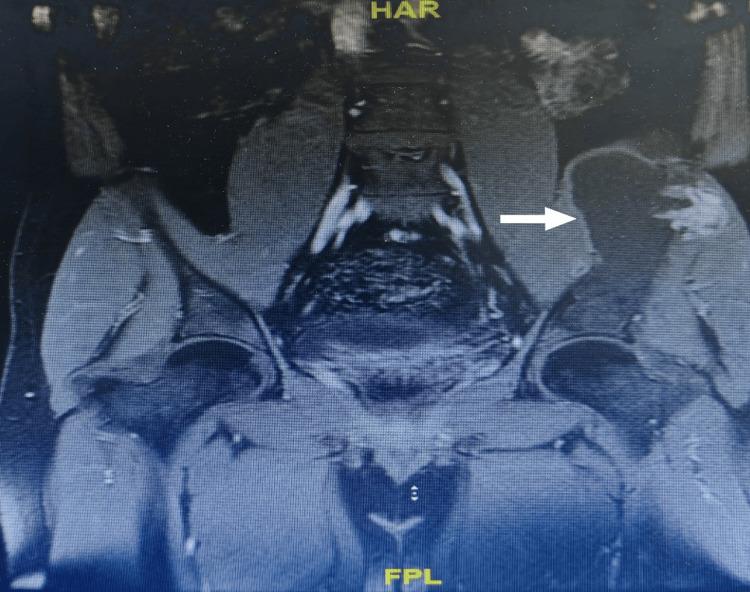

Lytic bone lesions pose significant diagnostic challenges due to their varied causes, ranging from malignancies to infections and benign conditions. Tuberculous osteomyelitis, though rare in non-endemic regions, remains an important consideration, particularly in patients from high-burden areas. A 35-year-old Sudanese male with a family history of tuberculosis (TB) presented with chronic left iliac pain that did not respond to nonsteroidal anti-inflammatory drugs (NSAIDs). Imaging revealed an expansile lytic lesion with cortical breaching, initially raising suspicion for malignancy. However, a biopsy showed necrotizing granulomatous osteomyelitis, though cultures - including those for were negative. Despite the lack of microbiological confirmation, the patient showed clinical and radiological improvement after starting empirical anti-TB therapy. This case highlights the need to consider tuberculous osteomyelitis in the differential diagnosis of lytic bone lesions, even in the absence of positive cultures, especially in individuals from endemic regions. Histopathological evidence of granulomas and a positive response to anti-TB therapy can support the diagnosis when microbiological tests are inconclusive. Greater awareness of this possibility is essential to prevent delays in treatment and unnecessary invasive procedures.

溶骨性骨病变因其病因多样,从恶性肿瘤到感染及良性疾病,带来了重大的诊断挑战。结核性骨髓炎在非流行地区虽罕见,但仍是一个重要的考虑因素,尤其是在来自高负担地区的患者中。一名35岁有结核病家族史的苏丹男性,出现慢性左髂骨疼痛,对非甾体抗炎药无反应。影像学检查发现一个有皮质破坏的膨胀性溶骨性病变,最初怀疑为恶性肿瘤。然而,活检显示为坏死性肉芽肿性骨髓炎,尽管包括结核菌培养在内的培养结果均为阴性。尽管缺乏微生物学确诊依据,但患者在开始经验性抗结核治疗后临床和影像学表现有所改善。该病例强调,即使在培养结果为阴性的情况下,在溶骨性骨病变的鉴别诊断中也需要考虑结核性骨髓炎,特别是在来自流行地区的个体中。当微生物学检查结果不明确时,肉芽肿的组织病理学证据及对抗结核治疗的阳性反应可支持诊断。提高对这种可能性的认识对于防止治疗延误和不必要的侵入性操作至关重要。